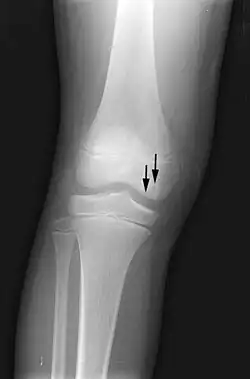

X-ray images of avascular necrosis in the early stages usually appear normal. In later stages it appears relatively more radio-opaque due to the nearby living bone becoming resorbed secondary to reactive hyperemia.[2] The necrotic bone itself does not show increased radiographic opacity, as dead bone cannot undergo bone resorption which is carried out by living osteoclasts.[2] Late radiographic signs also include a radiolucency area following the collapse of subchondral bone (crescent sign) and ringed regions of radiodensity resulting from saponification and calcification of marrow fat following medullary infarcts.

-

Radiography of total avascular necrosis of right humeral head. Woman of 81 years with diabetes of long evolution. -